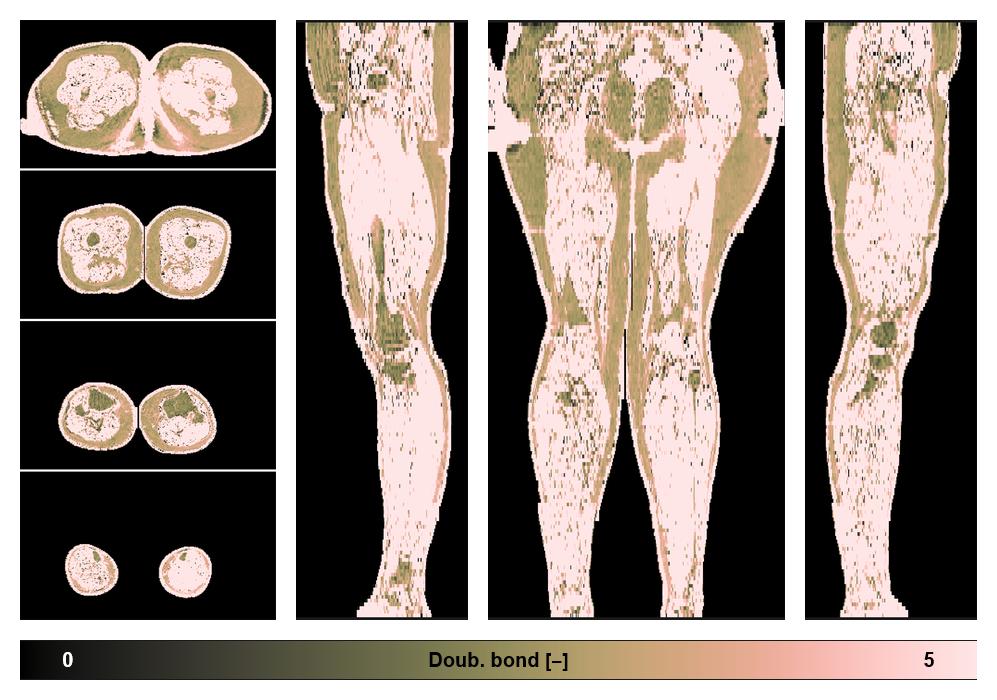

• Number of double bonds in subcutanious fat

Number of double bonds in subcutanious fat.